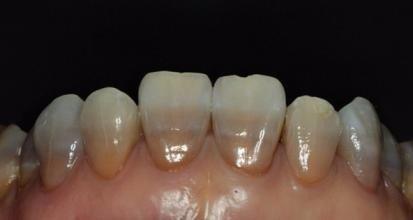

四环素牙的牙冠修复治疗适用于所有四环素牙,遮色效果佳。但需磨除较多的牙体组织,可能引起牙髓炎症。有些牙医认为要避免牙髓炎可能,在冠修复前应先将活髓牙变为无髓牙。冠修复目前一般采用的是烤瓷牙冠,其修复后色泽逼真。

3、瓷贴面修复

四环素牙的贴面治疗可适用于釉质发育不全者,但对于四环素着色严重的牙齿,效果不佳。该治疗需磨除少量牙釉质,在牙表面贴树脂、烤瓷等材料,制作要求较高,形态、色泽较佳,是非常流行的修复方法。

4、全瓷冠修复

全瓷冠不含有金属层,是由陶瓷切削炼制而成,因此显得更加自然、美观,修复后拥有像真牙一样的色泽。